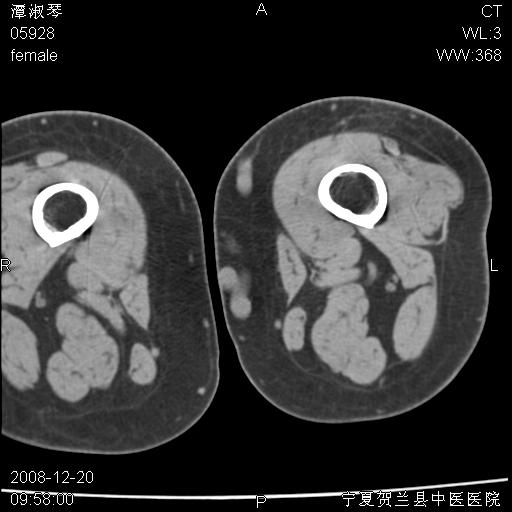

标题: CT17526:请各位看看是啥? [打印本页]

标题: CT17526:请各位看看是啥?

内生软骨瘤?骨梗死?

考虑内生软骨瘤可能性大

考虑-----骨梗死+退变

支持骨梗死,退行性骨关节病,膝关节积液.

考虑骨梗死可能性大

支持骨纤或内生软骨瘤或骨梗死,退行性骨关节病,膝关节积液.

骨梗死可能性大

左股骨下段骨梗死。双膝退变。

支持:内生软骨瘤或骨梗死!另:退行性骨关节病,膝关节积液。

左胫骨下端松质骨及髓腔内可见点片状高密度灶,骨皮质无明显膨胀及变薄。病变范围较长。支持骨梗死,退行性骨关节病,膝关节积液